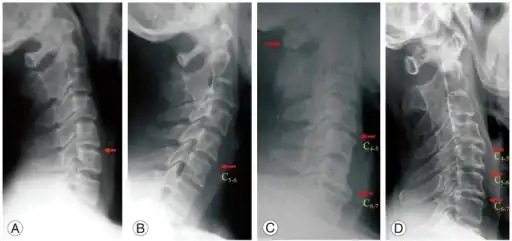

Spondylosis is the degeneration of the vertebral column from any cause. In the more narrow sense it refers to spinal osteoarthritis, the age-related wear and tear of the spinal column, which is the most common cause of spondylosis. The degenerative process in osteoarthritis chiefly affects the vertebral bodies, the neural foramina and the facet joints (facet syndrome). If severe, it may cause pressure on the spinal cord or nerve roots with subsequent sensory or motor disturbances, such as pain, paresthesia, imbalance, and muscle weakness in the limbs.

When the space between two adjacent vertebrae narrows, compression of a nerve root emerging from the spinal cord may result in radiculopathy (sensory and motor disturbances, such as severe pain in the neck, shoulder, arm, back, or leg, accompanied by muscle weakness). Less commonly, direct pressure on the spinal cord (typically in the cervical spine) may result in myelopathy, characterized by global weakness, gait dysfunction, loss of balance, and loss of bowel or bladder control. The patient may experience shocks (paresthesia) in hands and legs because of nerve compression and lack of blood flow. If vertebrae of the neck are involved it is labelled cervical spondylosis. Lower back spondylosis is labeled lumbar spondylosis. The term is from Ancient Greek σπόνδυλος spóndylos, "a vertebra", in plural "vertebrae – the backbone".

Diagnosis

There are multiple techniques used in the diagnosis of spondylosis, these are;

• MRI and CT scans are helpful for pain diagnosis but generally are not definitive and must be considered together with physical examinations and history.[5]

Decompression surgery: The vertebral column can be operated on from both an anterior and posterior approach. The approach varies depending on the site and cause of root compression. Commonly, osteophytes and portions of intervertebral disc are removed.[8]